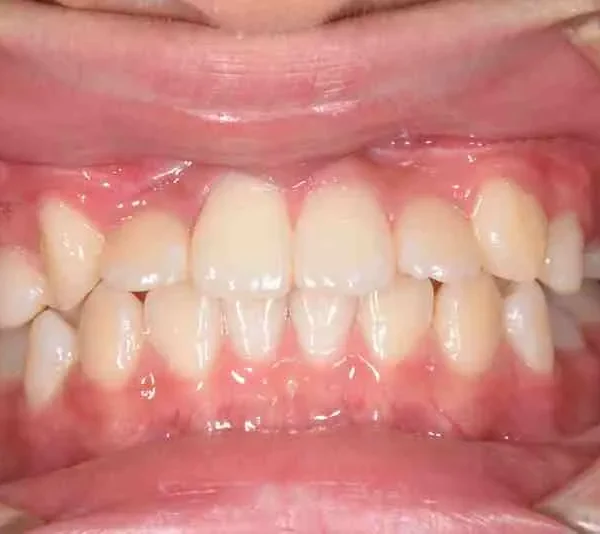

治療終了後

先ずは萌出スペースを確保してから開窓術を行い、犬歯を正しい方向へ誘導しました。

マルチブラケット装置は使わずに、最低限の必要な装置を使って目立たないように治療しました。

治療回数29回、2年10ヶ月の治療期間で矯正治療を終了しました。

主訴が改善され、ご満足頂きました。